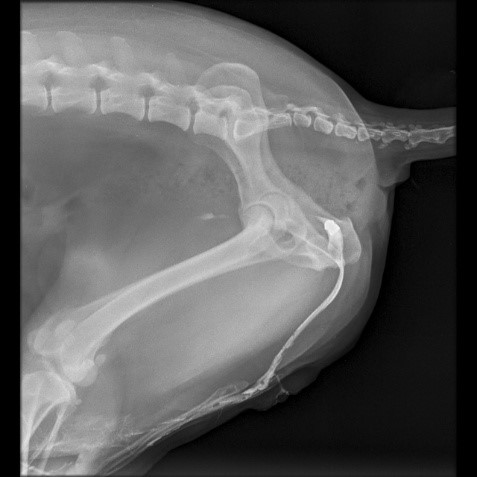

La obstrucción urinaria en caninos, habitualmente asociada a urolitiasis, puede tener causas inusuales, como la migración de cuerpos extraños. Se presenta el caso de un canino macho, castrado, con obstrucción uretral recurrente. El estudio radiográfico simple y contrastado evidenció la presencia de un proyectil intrauretral. Se realizó una retrohidropropulsión exitosa, seguida de la extracción quirúrgica del cuerpo extraño. Se presume que la migración tardía del proyectil se debió a la combinación de los movimientos corporales y la erosión progresiva de los tejidos, permitiendo su desplazamiento hasta la uretra. Este caso destaca la importancia de considerar etiologías atípicas en cuadros de obstrucción urinaria recurrente y resalta el valor diagnóstico de la imagenología. La retrohidropropulsión demostró ser una herramienta eficaz en la resolución inicial del cuadro. La similitud con casos descritos en medicina humana refuerza la necesidad de incluir la migración de cuerpos extraños como diagnóstico diferencial en pacientes con obstrucción urinaria, aportando al conocimiento de causas poco frecuentes en la medicina veterinaria